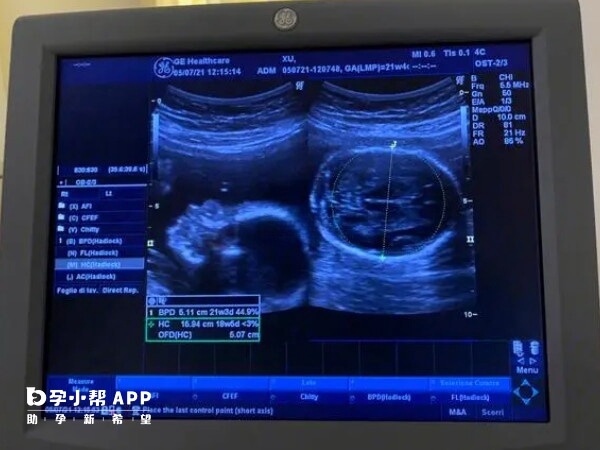

胎儿系统超声检查,也就是大家所说的大排畸,属于III级产科超声检查,是产前超声检查中最重要的一个项目。在孕检中,双胞胎大排畸检查难度之所以比较大,原因如下:

大排畸需对每个胎儿的颅脑、心脏、脊柱、四肢等部位逐一检查,双胞胎的检查量是单胎的数倍((约60-90分钟))。若胎儿不配合,医生需花费更多时间等待合适体位,检查时长可能延长至1小时甚至更久,对孕妇和医生的体力和耐心都是挑战。

双胞胎大排畸对超声设备的分辨率和医生的技术经验要求极高。高分辨率设备能更清晰显示胎儿细微结构,而经验丰富的医生需具备快速识别异常的能力,同时区分两个胎儿的特征,避免混淆。